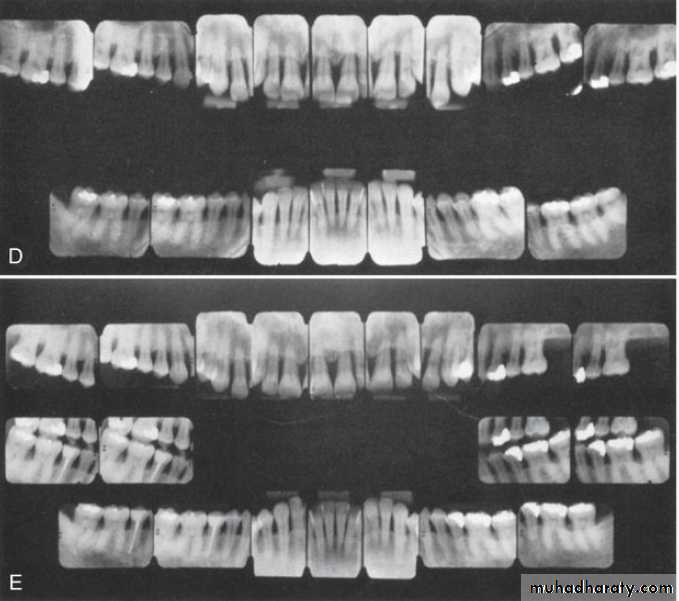

Radiographic examination must be individualized, depending on the initial severity of the case and the findings during the recall visit. These are compared with findings on previous radiographs to check the bone height and look for repair of osseous defects, signs of trauma from occlusion, periapical pathologic changes, and caries.

Recurrence of Periodontal DiseaseOccasionally, lesions may recur, which is often due to inadequate plaque/biofilm control on the part of the patient or failure to comply with recommended SPT schedules.

1. Inadequate or insufficient treatment that has failed to remove all of the potential factors favoring biofilm accumulation. Incomplete calculus removal in areas of difficult access is a common source of problems.2. Inadequate restorations placed after the periodontal treatment was completed.